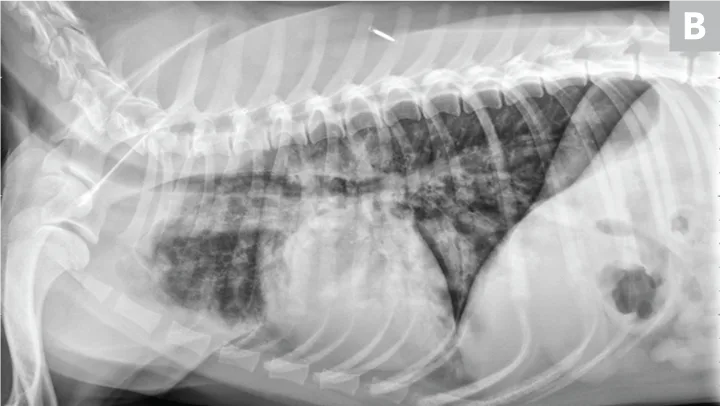

FIGURE 1

(A) Bronchopneumonia. Cranioventral distribution of alveolar disease with air bronchograms. (B) A patchy distribution can be observed on the lateral projection. The changes overlying the heart may be missed in subtle cases.